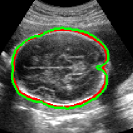

As mentioned in Sec. 3.2, it is crucial for our brain extraction network to work consistently regardless of the orientation of the brain within the US volume. This can be qualitatively observed in Fig. 3, which shows the outline of the brain-extraction prediction and the corresponding ground-truth, in red and green respectively, for six different 3D US volumes. These volumes have been selected to demonstrate the amount of variation between each scan, with the position of the fetus inside the mother as well as the position of the brain in respect to the scan varying drastically from case to case.

As shown in Fig. 3 , the network’s prediction is remarkably close to the ground-truth, regardless of the position of the brain in the volume. It also manages to accurately predict the location of the brain when this is partially obscured either by the cropping or the shape of the ultrasound beam.